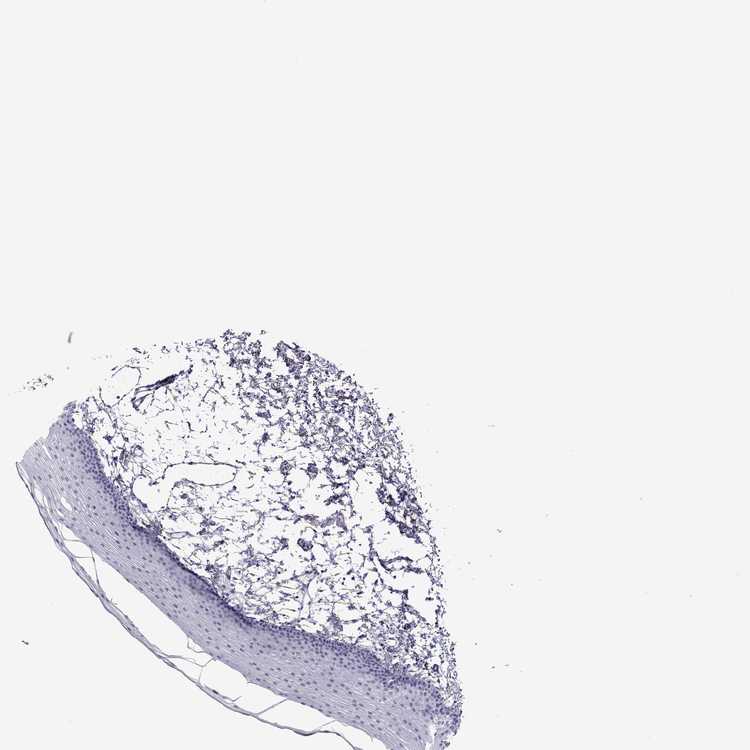

TISSUE PRIMARY DATA ORAL MUCOSA Show tissue menu

ORAL MUCOSA - Antibody stainingi

Antibody staining in the annotated cell types in the current human tissue is reported as not detected, low, medium, or high, based on conventional immunohistochemistry profiling in selected tissues. This score is based on the combination of the staining intensity and fraction of stained cells.

Each image is clickable and will lead to virtual microscopy that enables deeper exploration of all samples and also displays staining intensity scores, fraction scores and subcellular localization as well as patient and tissue information for each sample.

Antibody HPA066468

Squamous epithelial cells Not detected